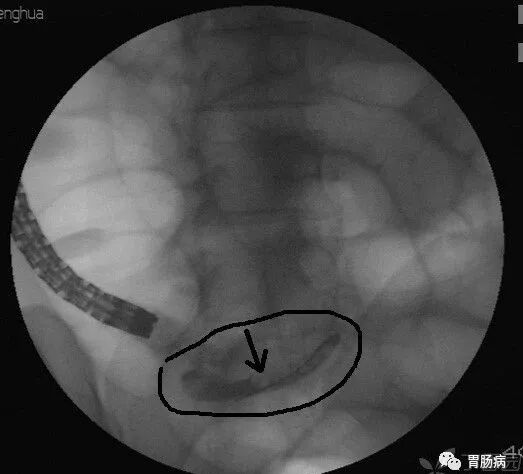

2.内镜逆行性阑尾造影术(endoscopic retrograde appendicography,ERA):

X线下,阑尾腔内注入造影剂显示阑尾腔的形态(椭圆形线圈),如有粪石(黑箭头),则行球囊取石术。并确认有无阑尾穿孔。